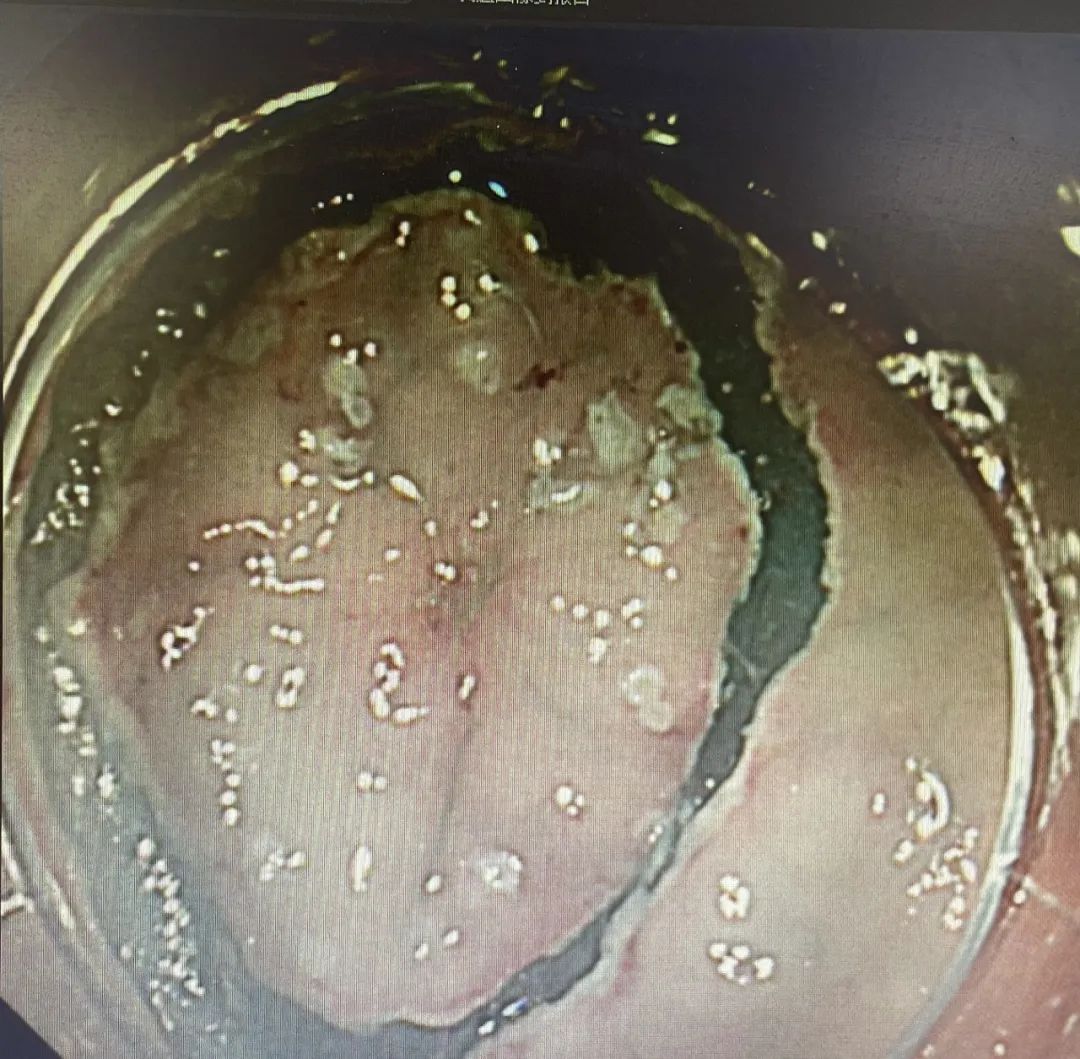

【技術(shù)領(lǐng)航】精準(zhǔn)篩查消化道早癌!早發(fā)現(xiàn)、早治療,90%消化道癌癥完全可以治愈

消化界有這樣一句話:“發(fā)現(xiàn)一例早癌,挽救一個生命,拯救一個家庭!”消化道癌癥防治的唯一出路為“三早”,即:早期發(fā)現(xiàn)、早期診斷、早期治療。世界衛(wèi)生組織(WHO)明確指出:早期發(fā)現(xiàn)是提高癌癥治療率的關(guān)鍵。只要早期發(fā)現(xiàn),90%的癌癥完全可以治愈!